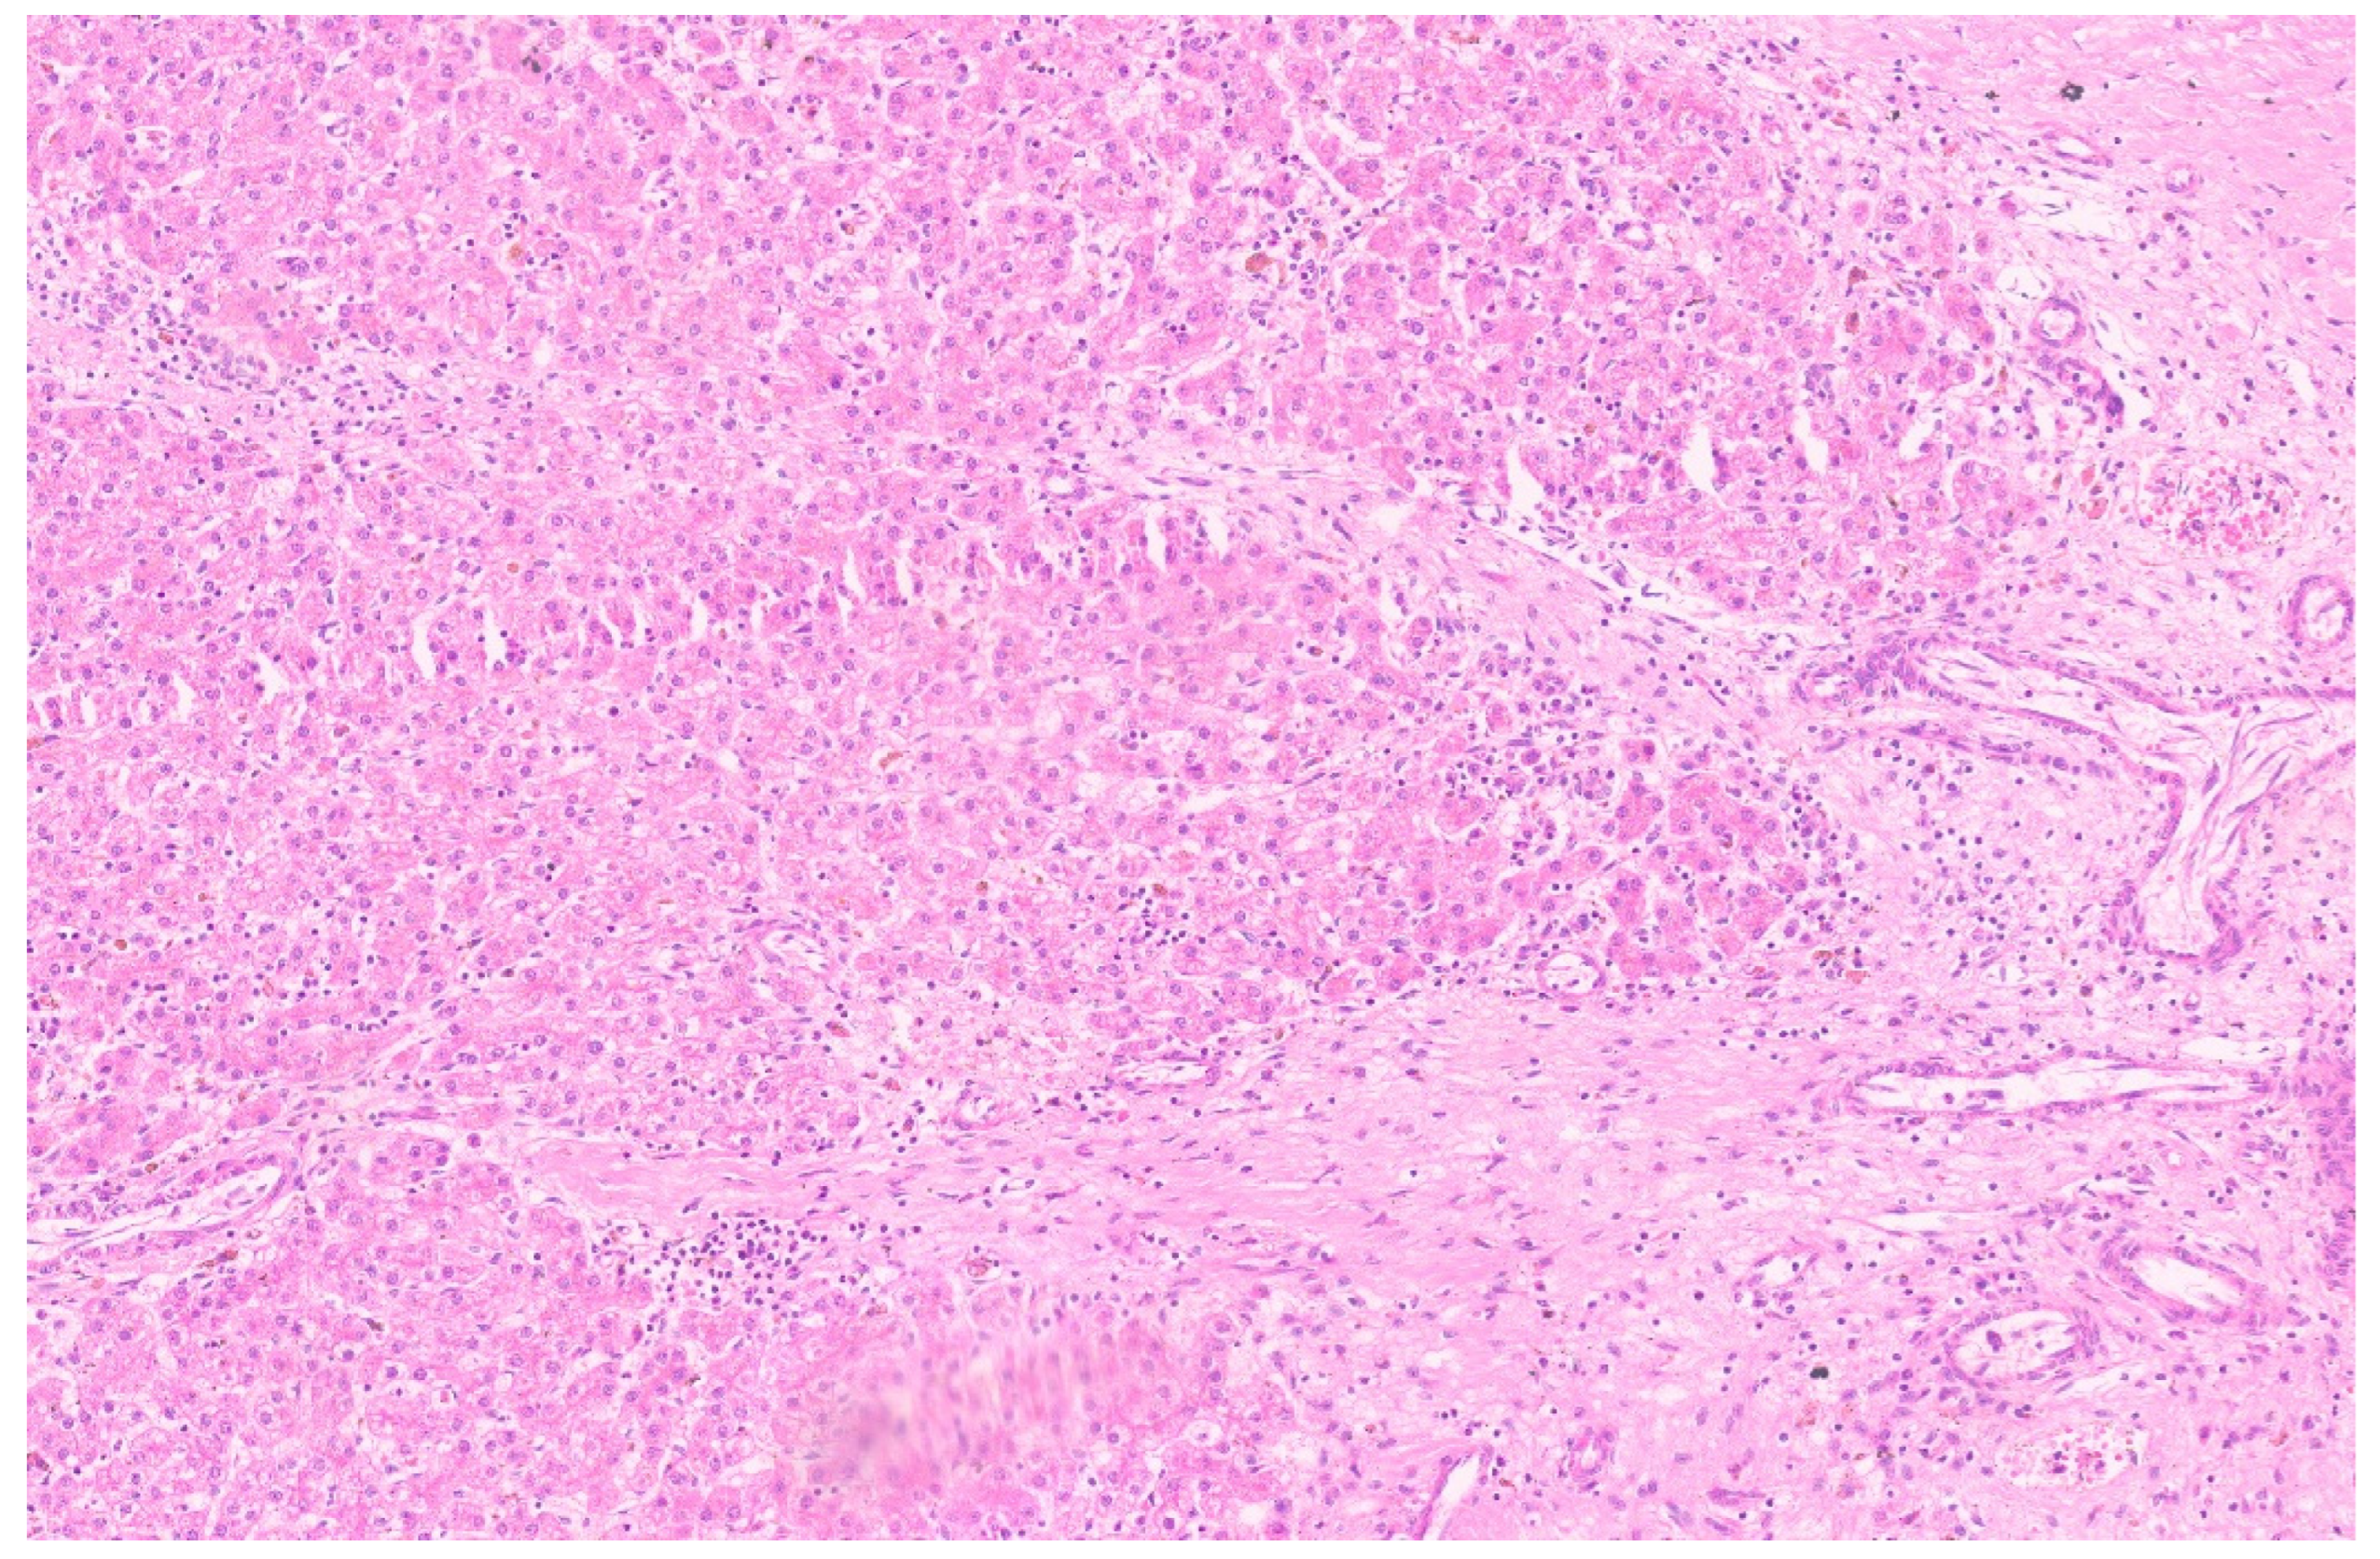

10.3. Pathology

15.3. Pathology